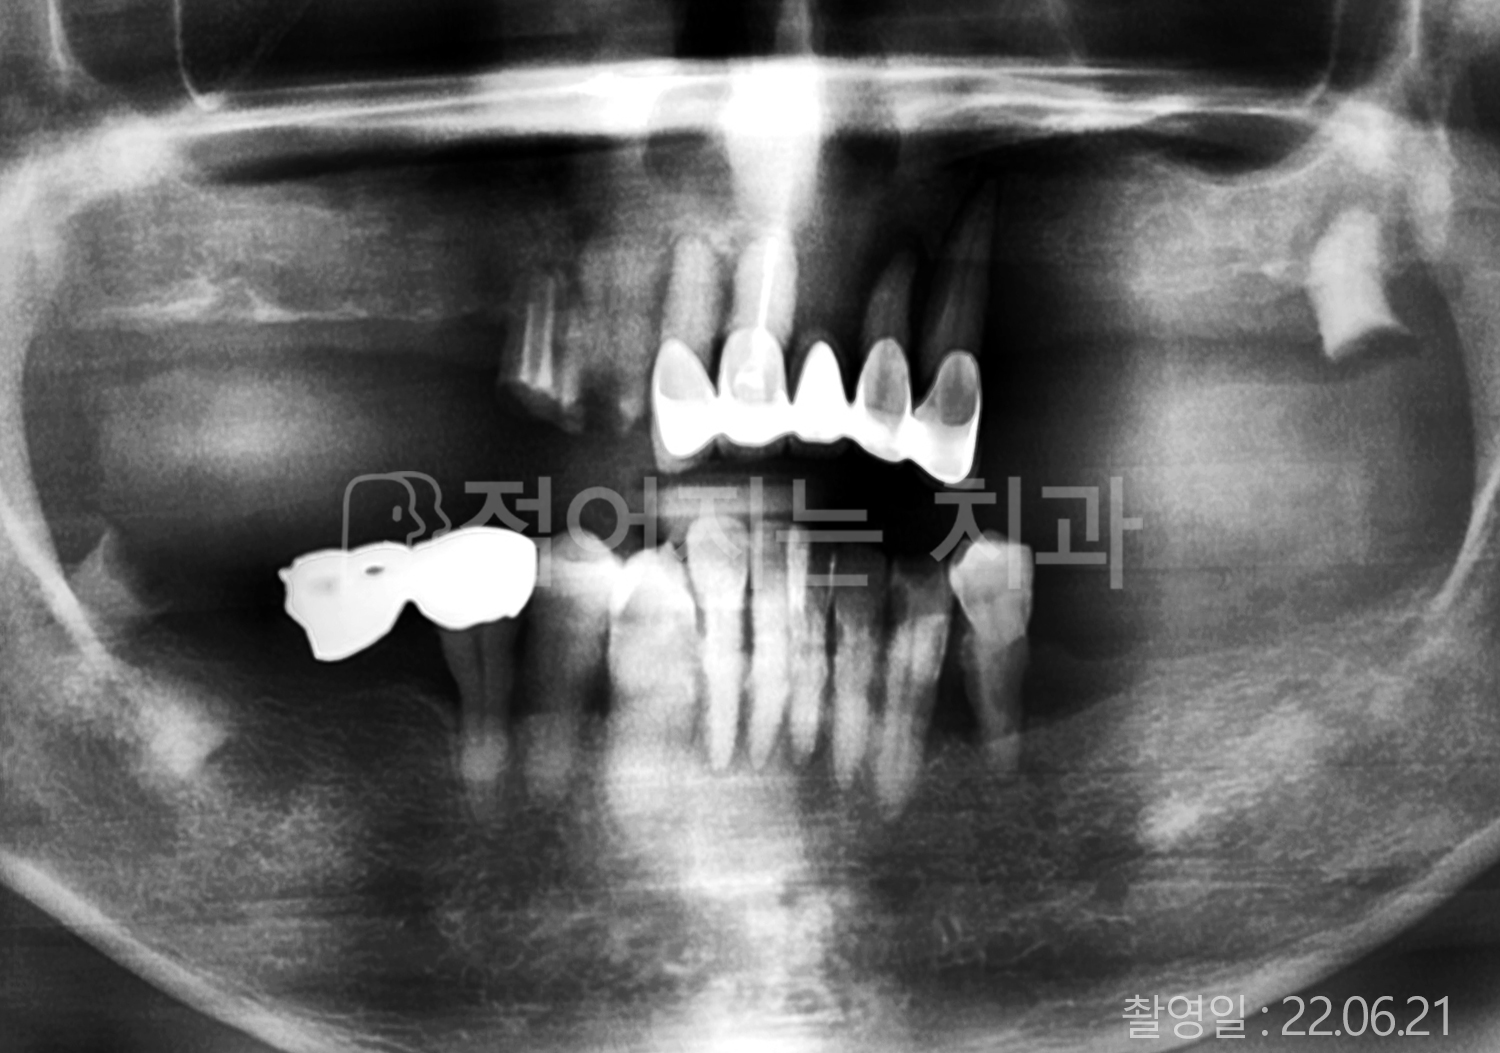

• 60대 고혈압, 고지혈증 전체치아 10개 이상 임플란트

• 70대 전체치아 10개 이상 임플란트

• 60대 전체치아 10개 이상 임플란트

• 50대 전체치아 10개 이상 임플란트

• 50대 고혈압, 고지혈증 전체치아 10개 이상 임플란트

• 60대 고혈압, 당뇨, 고지혈증 전체치아 10개 이상 임플란트

• 80대 고혈압, 당뇨, 골다공증 전체치아 10개 이상 임플란트

• 60대 고혈압 전체치아 10개 이상 임플란트

• 60대 고지혈증 전체치아 10개 이상 임플란트

• 60대 당뇨 전체치아 10개 이상 임플란트